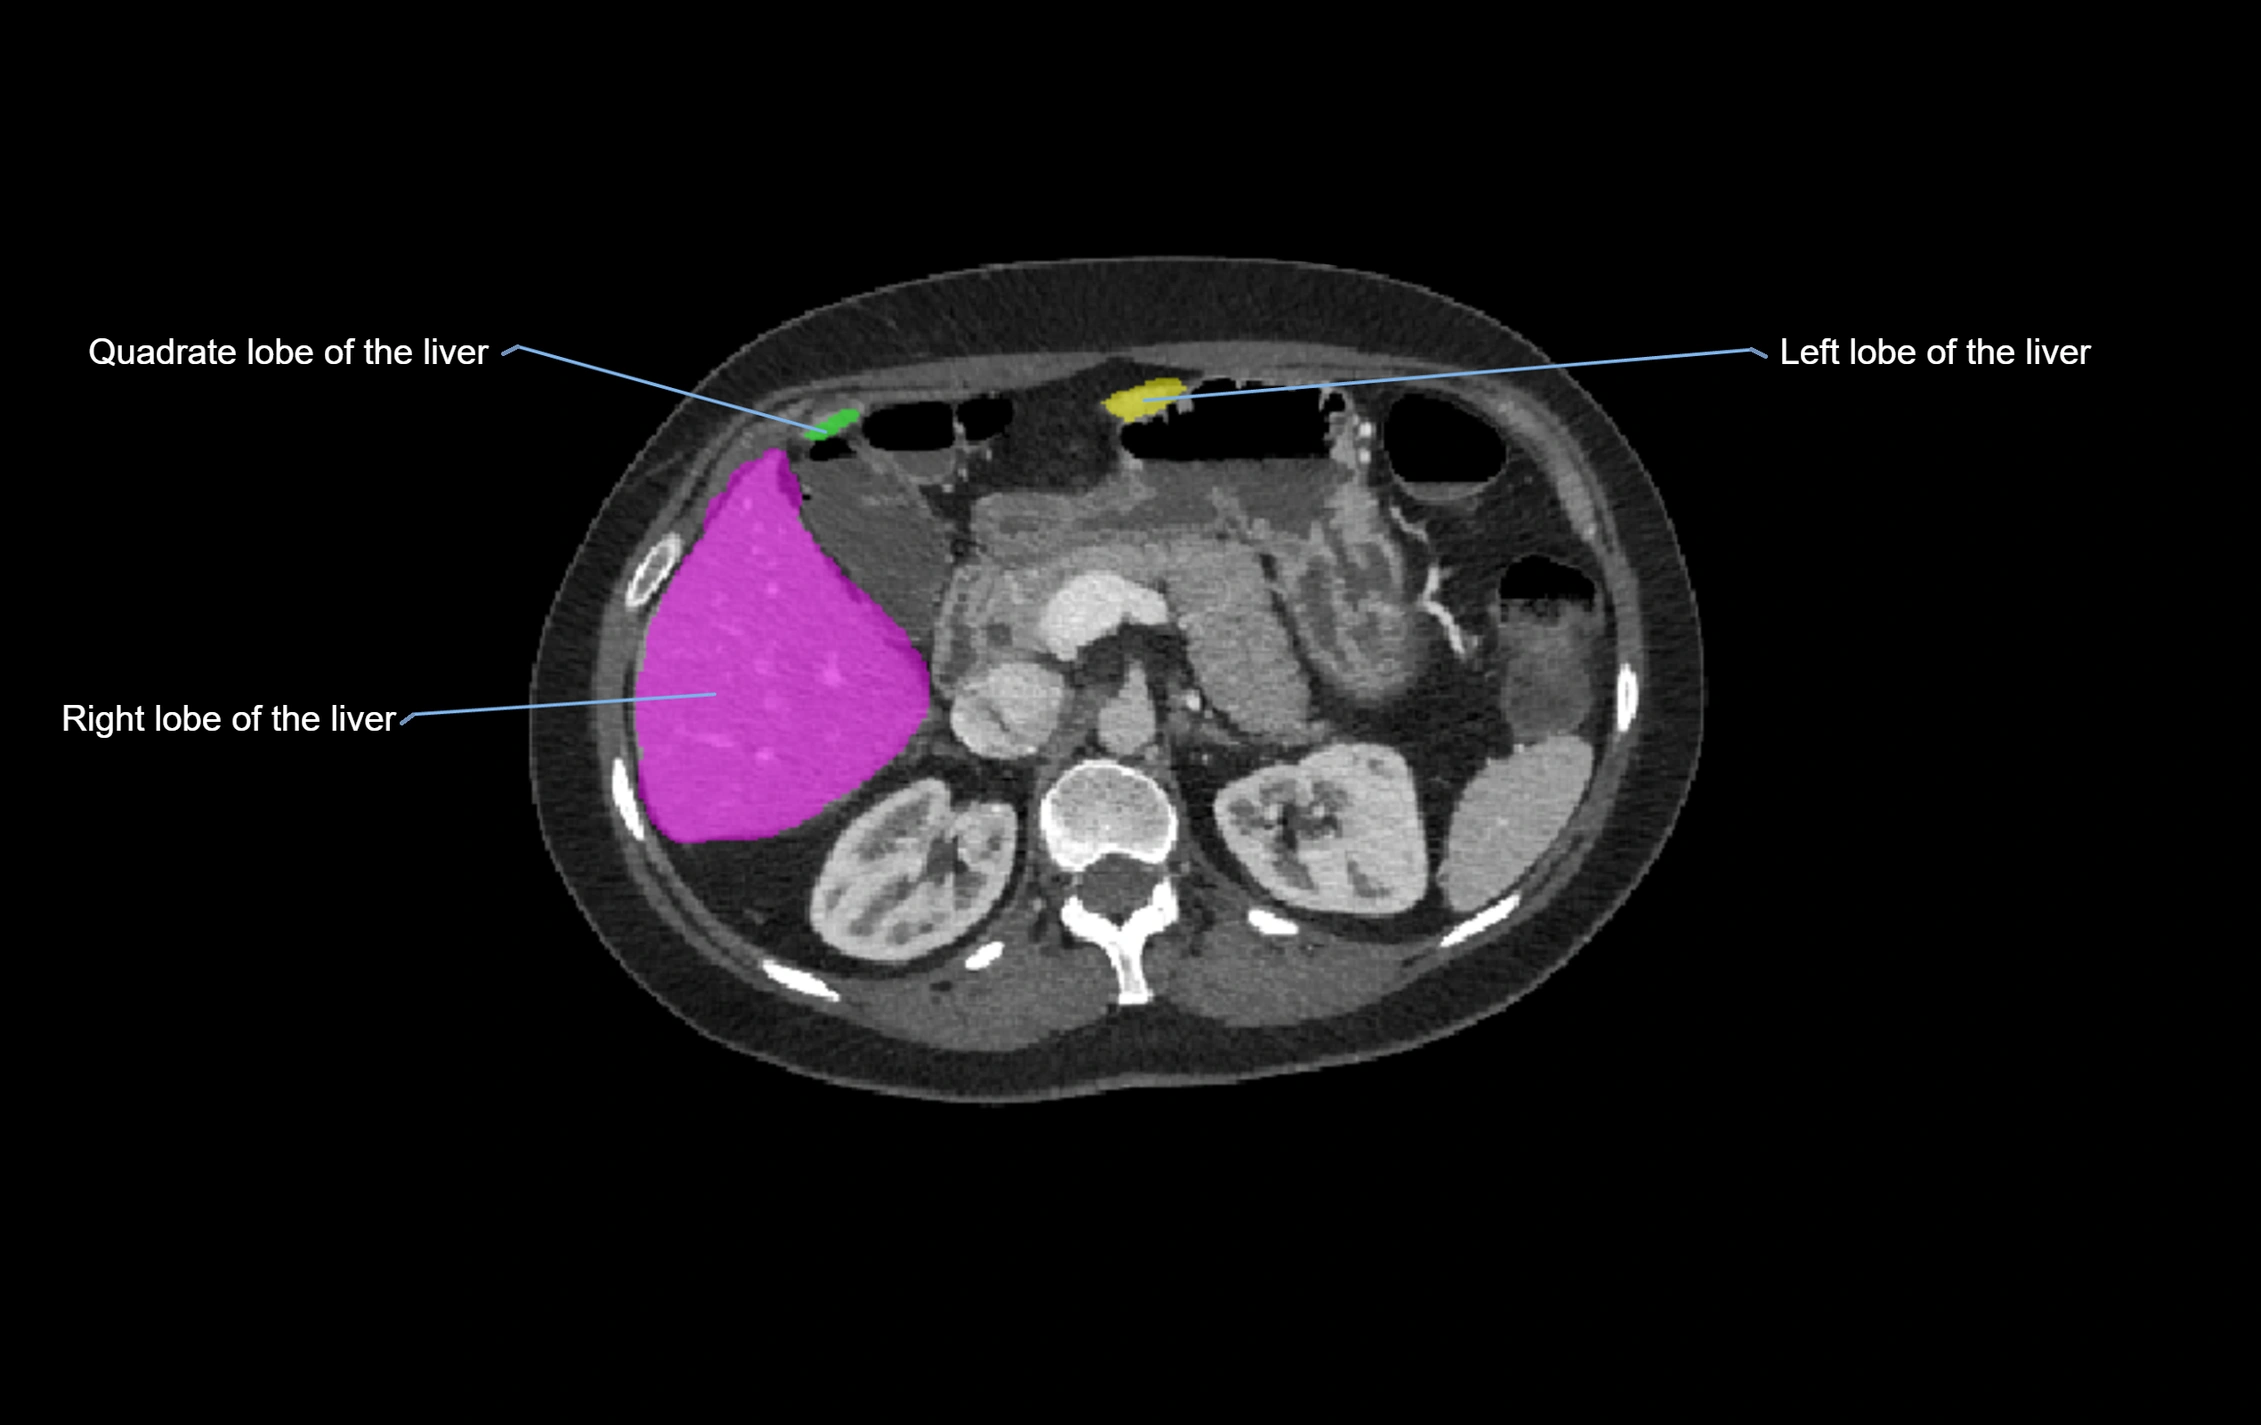

CT Image

image